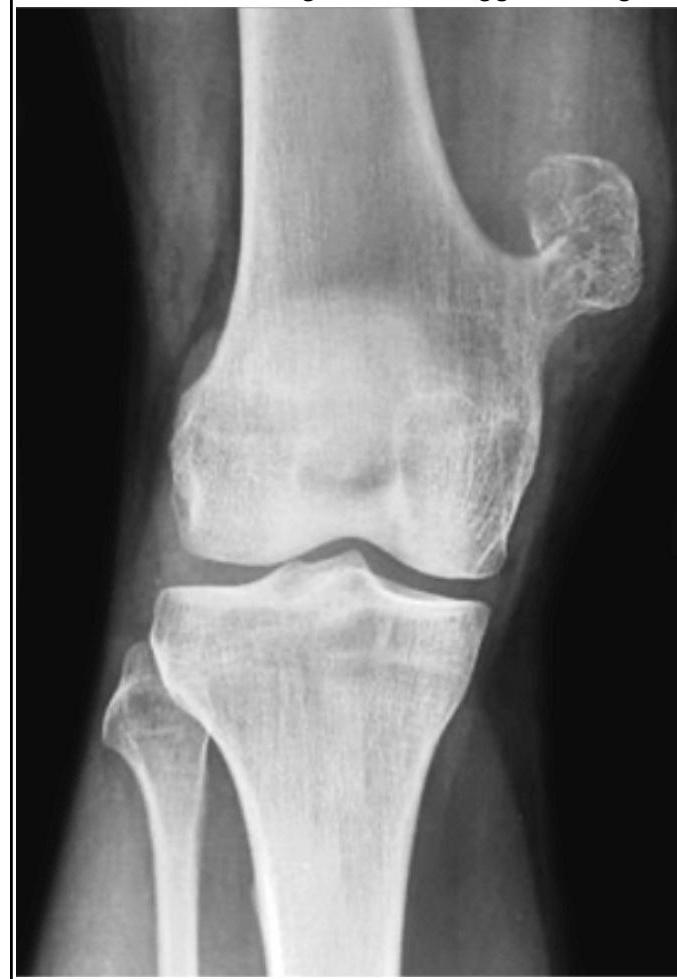

A 18-year-old boy presents with tenderness, warmth over the bone, and fever, ESR and CRP levels. The radiograph is shown below. What is the most likely diagnosis?

Explanation: ***Osteomyelitis*** - The clinical presentation of **fever, localized tenderness, and warmth** with elevated **ESR and CRP** levels in an 18-year-old is highly suggestive of **osteomyelitis**, an infection of the bone. - Radiographs in acute osteomyelitis may show soft tissue swelling, periosteal reaction, and areas of **bone destruction**, which can be subtle early in the infection. *Ewing's sarcoma* - This typically presents with local pain and swelling, and can also cause fever and elevated inflammatory markers. - However, characteristic radiographic findings such as an **"onion skin" periosteal reaction** or a **"moth-eaten" appearance** are not clearly visible here. *Osteosarcoma* - This is a primary malignant bone tumor often seen in adolescents, presenting with localized pain and swelling. - Radiographic features typically include a **Codman triangle**, **sunburst appearance**, or a **mixed lytic and blastic lesion**, which are not seen in this image. *Giant cell tumor* - Usually occurs in **young adults (20-40 years old)**, not typically in an 18-year-old, and presents with pain and swelling around the joint. - Radiographically, it is characterized by an **eccentric lytic lesion** in the **epiphysis or metaphysis** of long bones, often described as a **"soap bubble" appearance**, which is not depicted here.